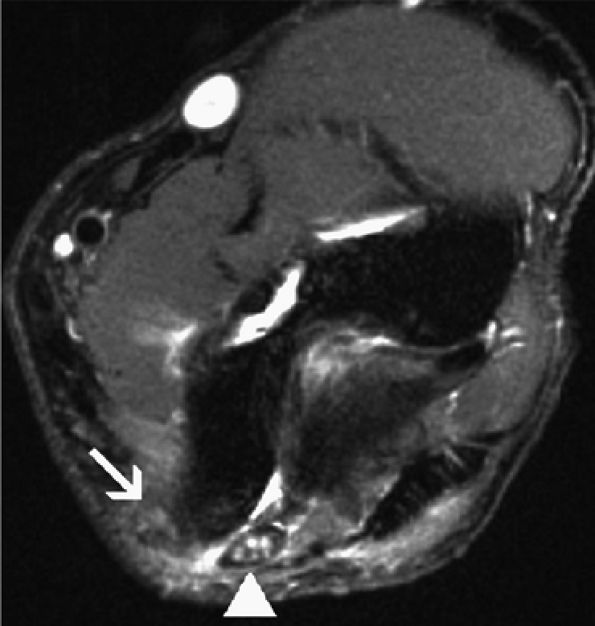

|

FIGURE 12.22 ● Compressive ulnar neuropathy caused by a displaced fracture fragment. Axial fast spin-echo T2-weighted image shows an old, displaced, non-united avulsion fragment (asterisk) of the medial humeral epicondyle resulting in mass effect and secondary subluxation of the ulnar nerve (arrow).